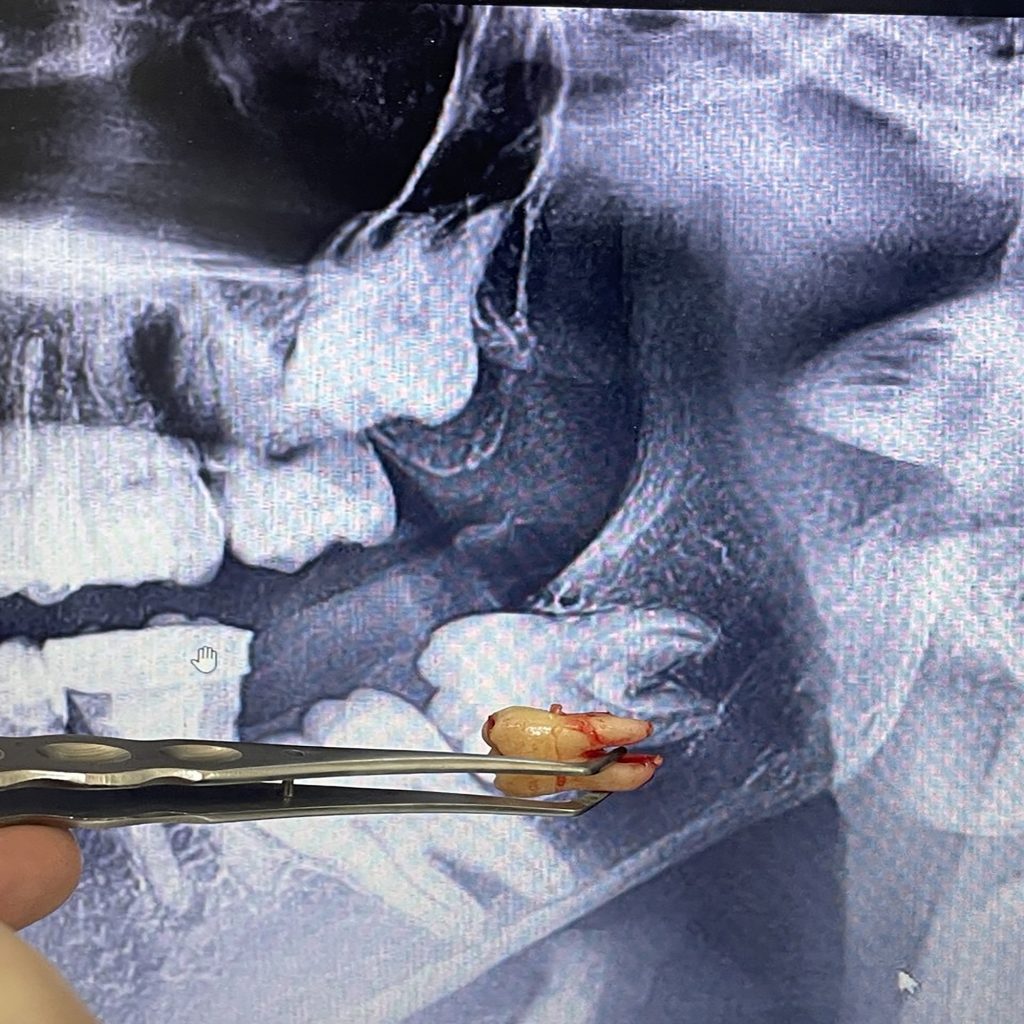

surgical extraction

Gentle precision for a smooth, worry-free recovery.